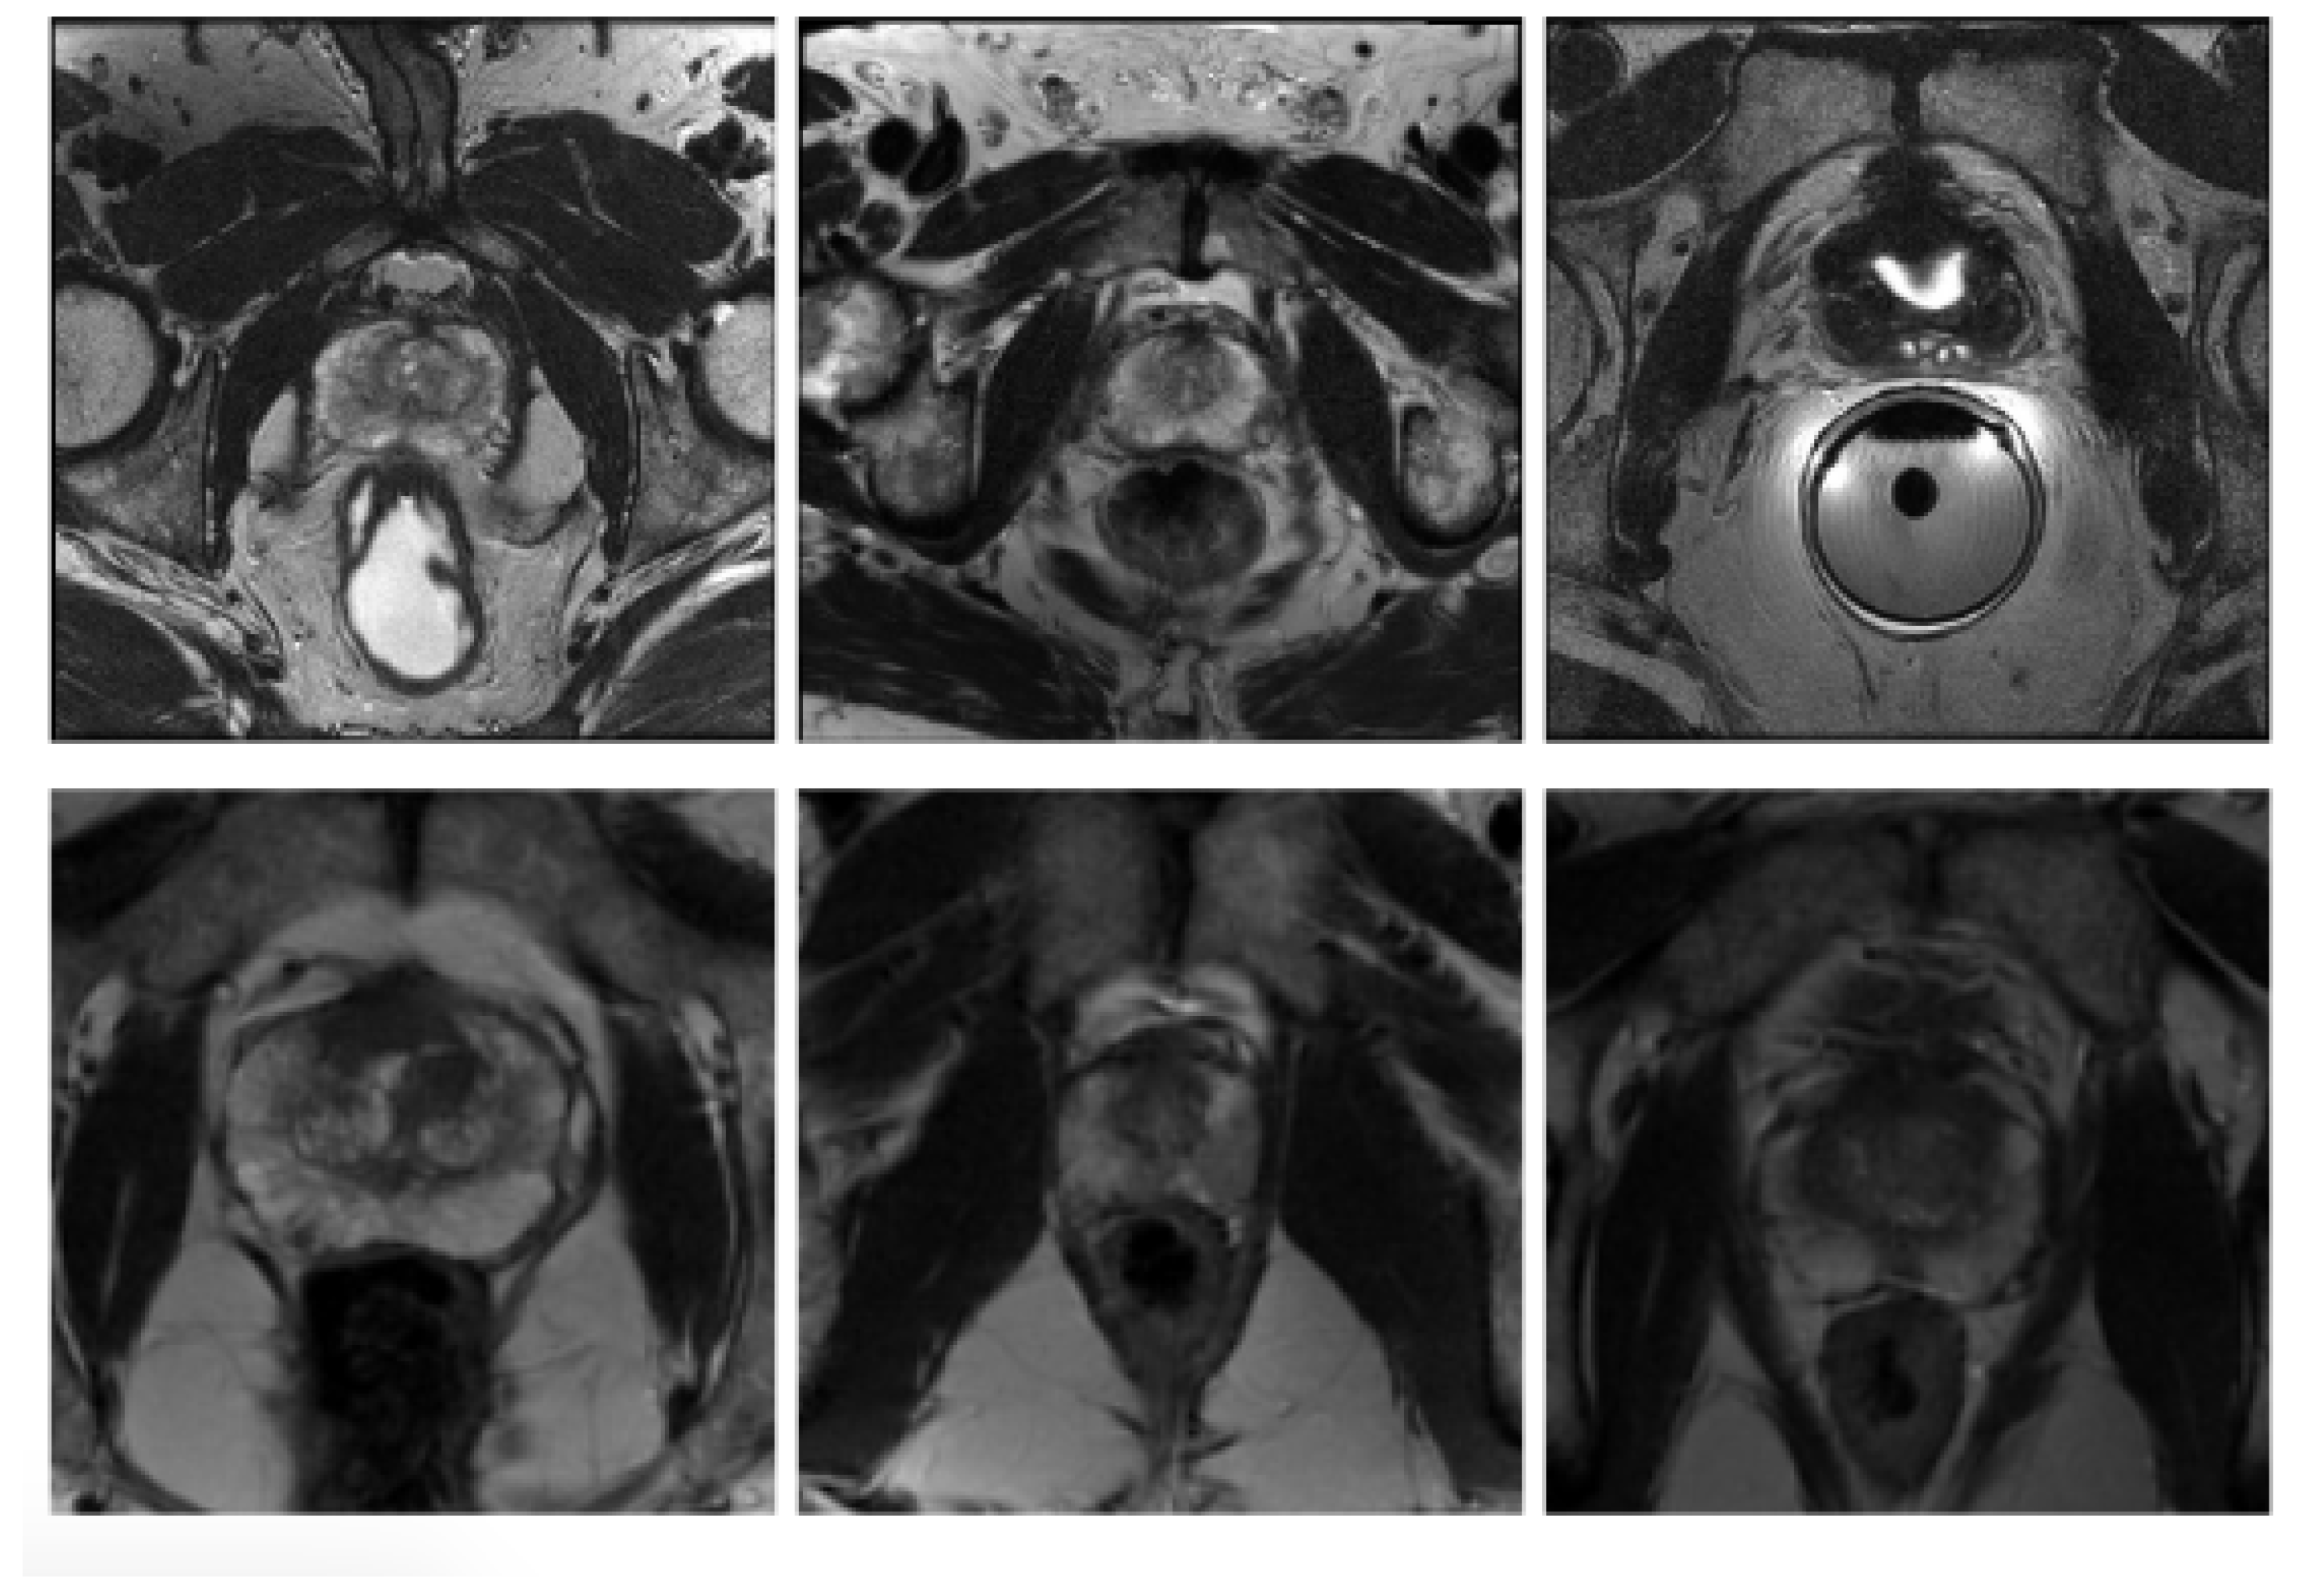

In order to examine the generalisability of the models on another representative set of MR images acquired in a clinical setting, the publicly available dataset (PROMISE12) [25] was used. This dataset contains 50 cases including T2-weighted MR images of the prostate. This dataset is multi-center and multi-vendor and has different acquisition protocols, with various prostate sizes and appearances. Details of the acquisition protocols for the different centers is explained by Litjens et al. [25]. Due to different MRI protocols (e.g., differences in slice thickness, magnet strength, with/without endorectal coil), the quality of the images was different in this cohort. Figure 2 shows some slices from different data cohorts to show appearance differences. There is a spread in prostate sizes and appearance in all images in our clinical cohort and the public dataset.

Figure 2.

Some slices from different data cohorts to show appearance differences with T2 modality. First row: PROMISE12 dataset. Second row: our clinically collected dataset.